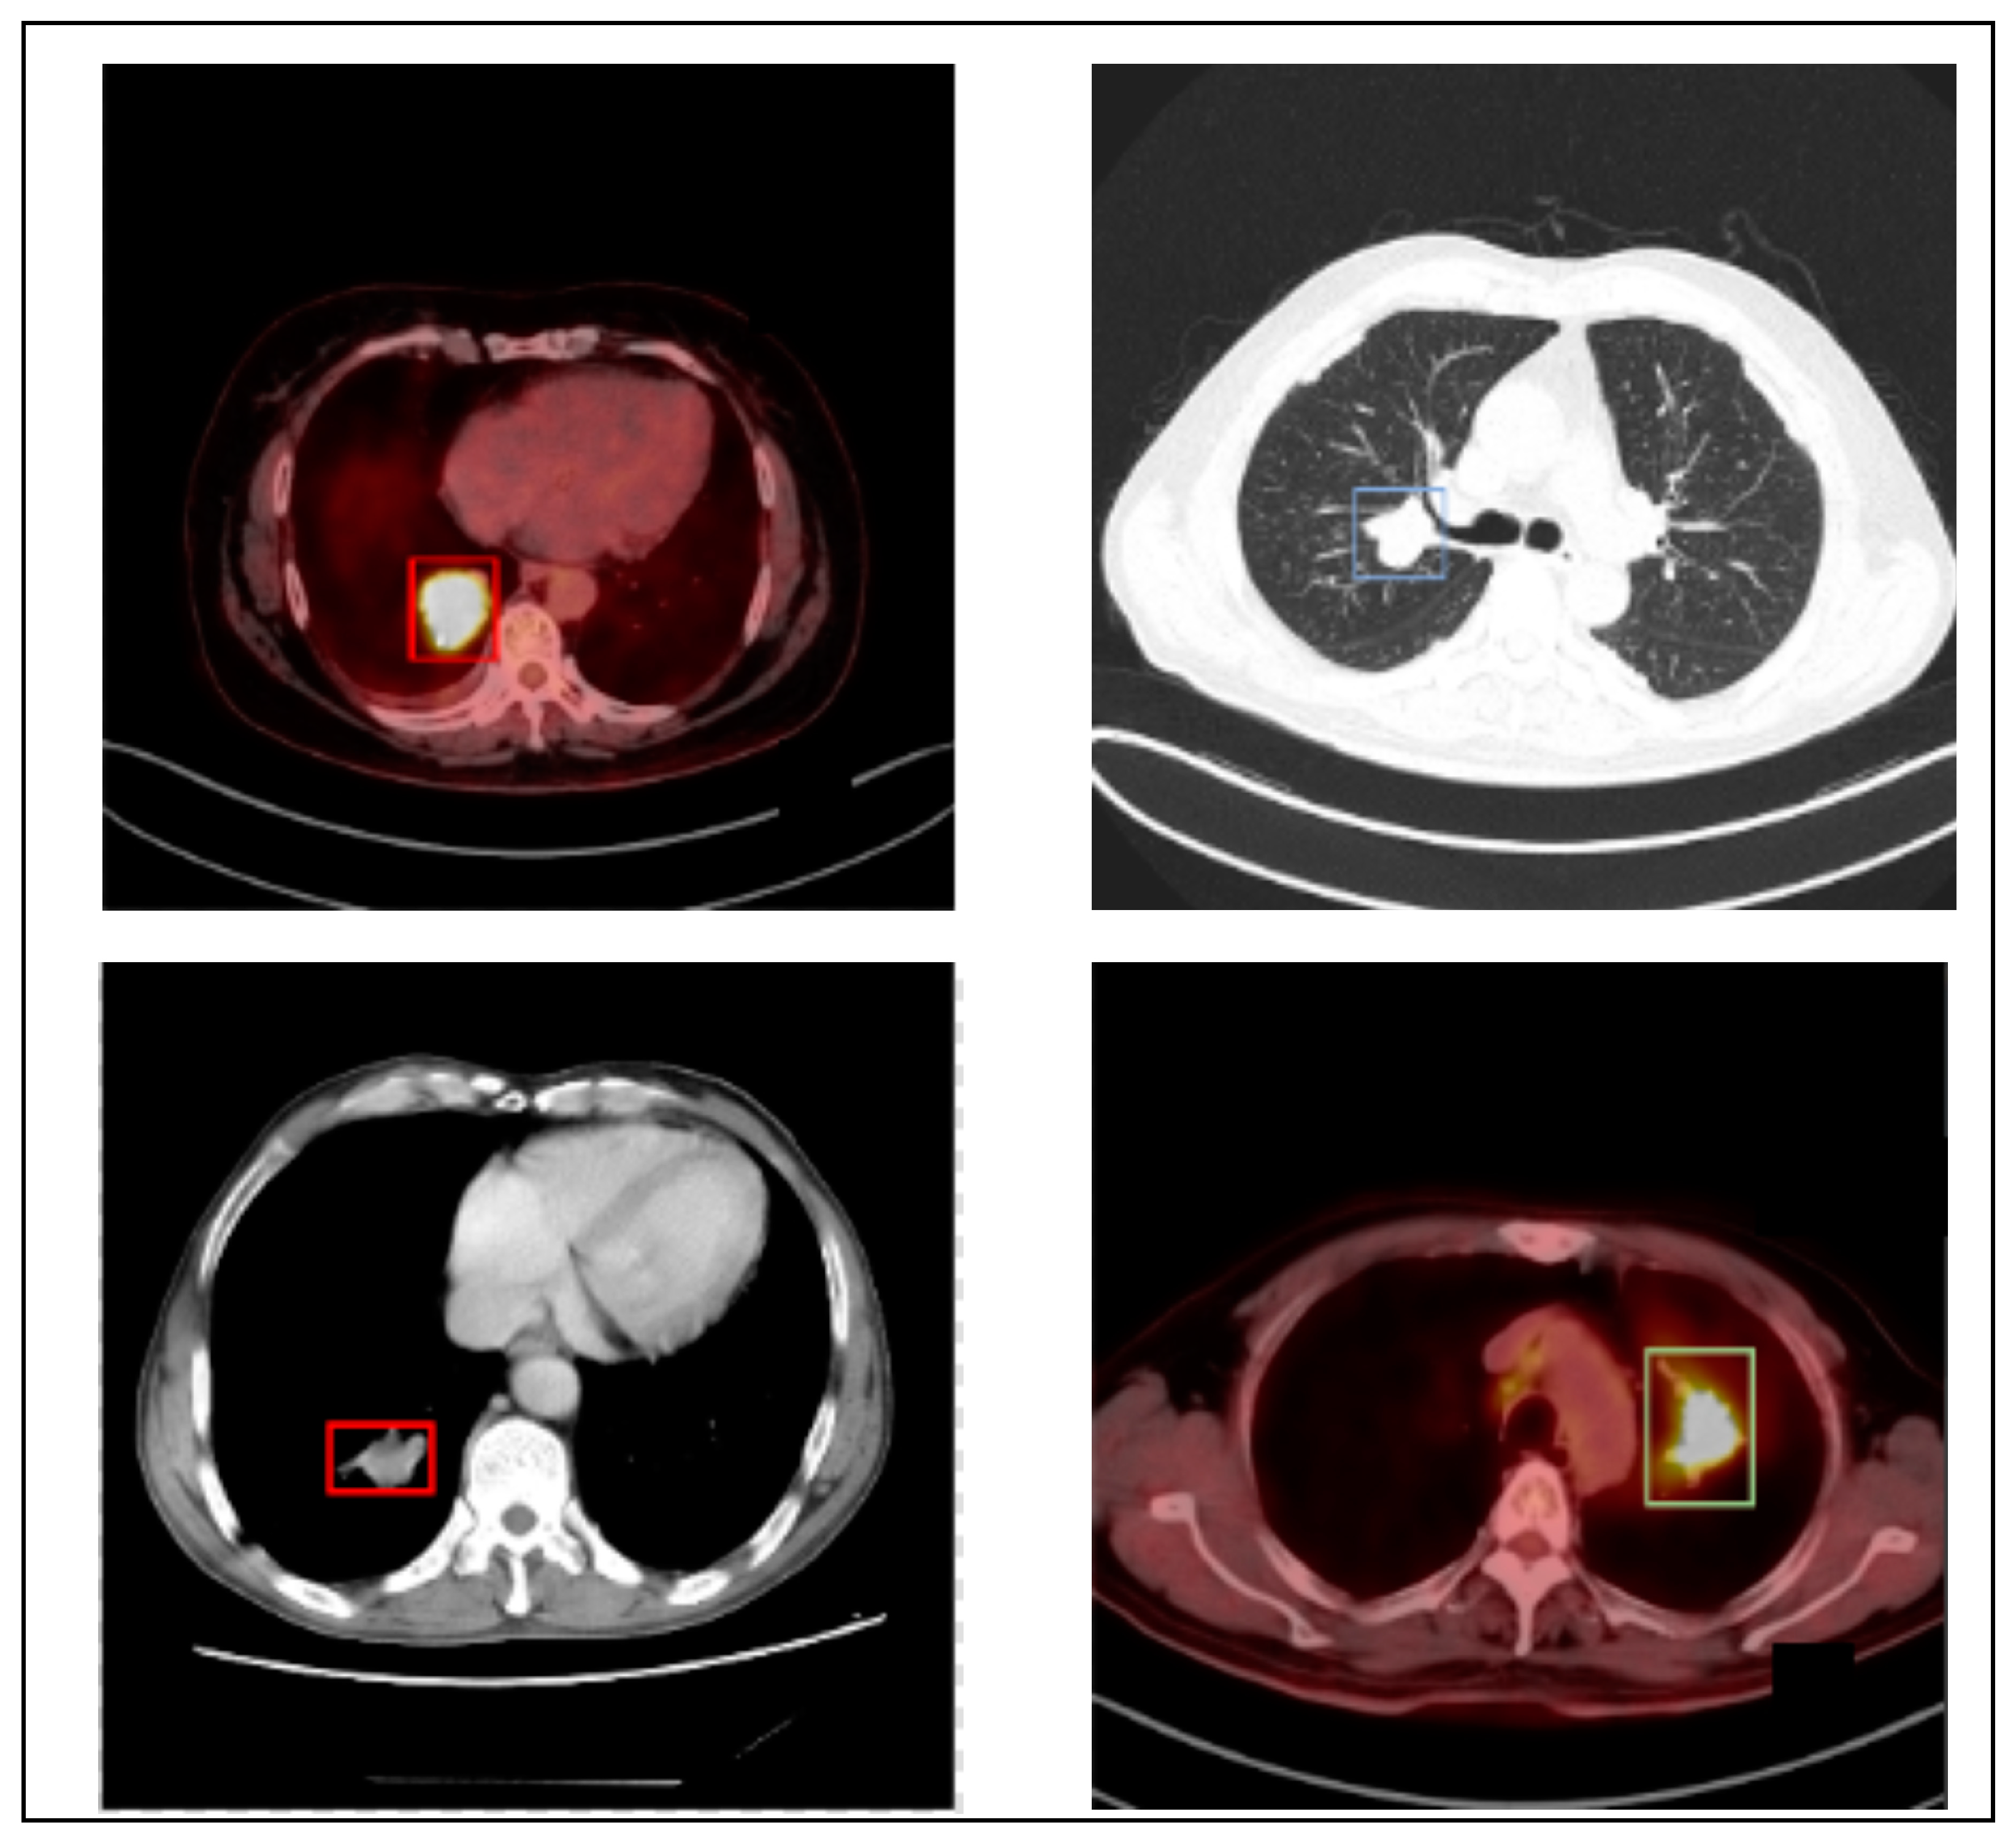

The author utilizes the PET/CT (Lung-PET-CT-Dx) dataset to generalize the proposed LC detection model. Lung-PET-CT-Dx is a recently developed dataset that comprises 31,562 annotated images. It is publicly available in the repository [36,37]. The images were retrospectively collected from multiple healthcare centers across China. The computer center and cancer institute, Harbin Medical University in Harbin, China, supported the dataset owners in obtaining permission to collect the PET/CT images. In addition, the patient’s personal information was not included in the dataset. The dataset contains CT and PET-CT DICOM images of LC patients. It provides XML annotation files to indicate tumor location and bounding boxes. The tissue histopathological diagnosis was used for the patients’ classification. The CT image resolution was 512 × 512 pixels at 1 mm × 1 mm, and the PET image resolution was 200 × 200 pixels at 4.07 mm × 4.07 mm. Five academic thoracic radiologists with expertise in LC detection were employed to annotate the tumor location. The Labellmg 1.4.0 package was used to capture the annotation. The images were broadly classified into adenocarcinoma (A), small cell carcinoma (B), large cell carcinoma (E), and squamous cell carcinoma (G). However, the dataset is highly imbalanced. Table 1 offers the dataset characteristics. Figure 2 highlights the sample LC images.

Figure 2. Sample images.